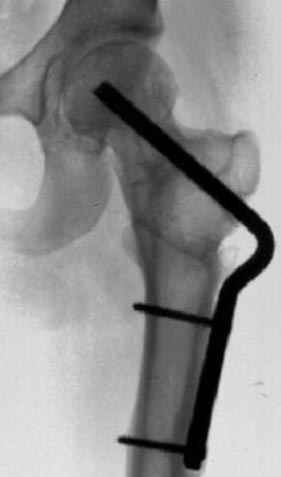

На рисунке N1 предоперационный план лечения ложного сустава шейки бедра- линия ложного сустава, угол и направление введения импланта, клиновидная остеотомия в градусах и миллиметрах, второй снимок после коррекции, расчет, на сколько удлиняется конечность и размеры импланта;

N3 рисунок окончательный снимок, после операции моя рентгенограмма должен выглядеть примерно как эта картина. На N4 снимке клин перед удалением; N5 послеоперации 3 нед.; N6 окончательная рентгенограмма.